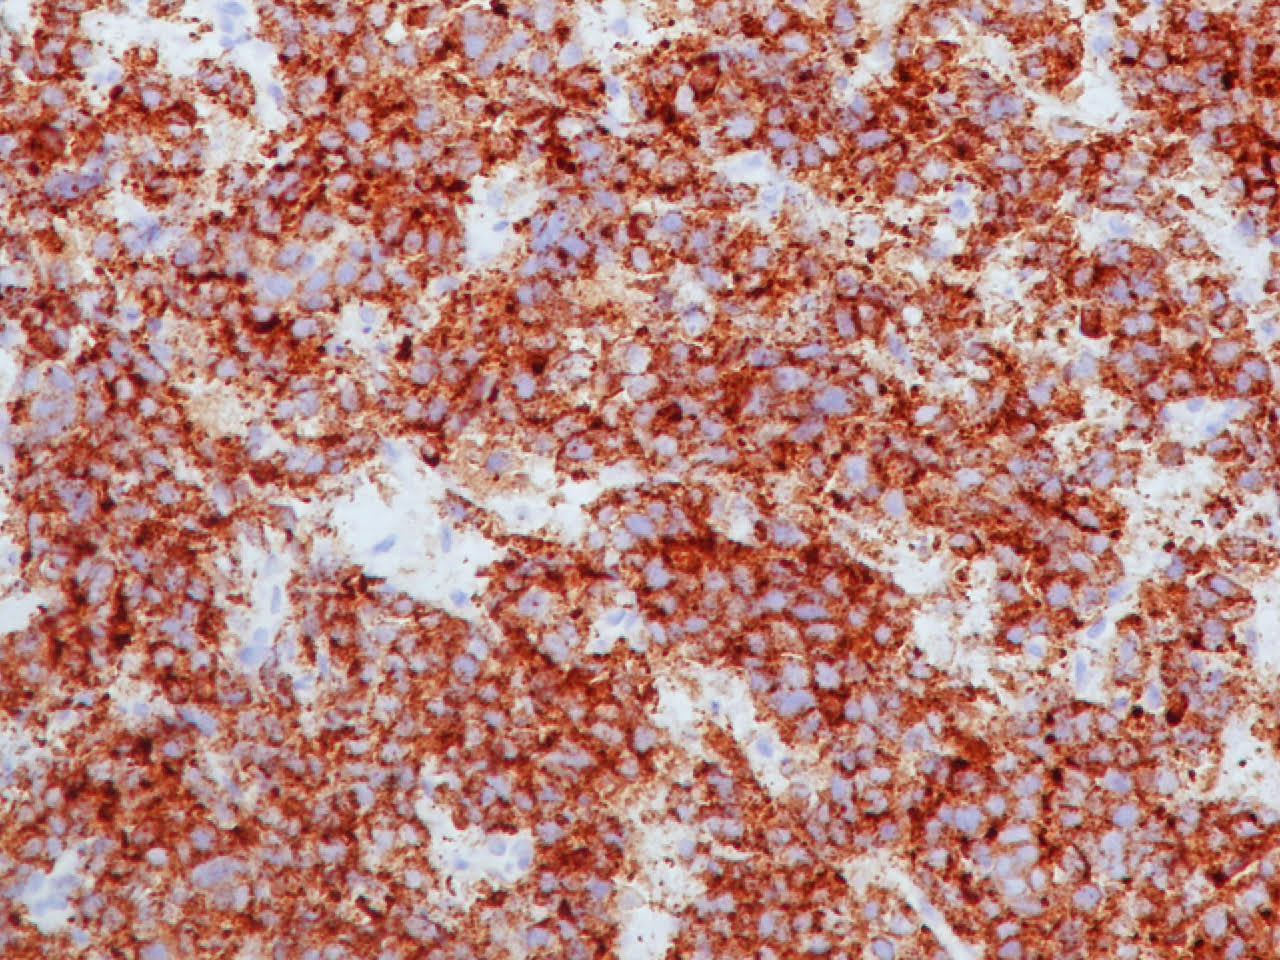

Microscopic (histologic) images

Contributed by Ioanna Abba Nteka, M.D., Aggeliki Cheva, M.D., Ph.D., Antonia Loukousia, M.D., Roseann Wu, M.D., M.P.H. and Kyriakos Chatzopoulos, M.D., Ph.D.

Positive stains

- Neuroendocrine markers, usually at least 2 focal to diffuse (chromogranin, synaptophysin, CD56), caution if CD56 is the only neuroendocrine marker expressed

- Cytokeratins AE1 / AE3, CAM5.2

- Variable CK7 and 34 beta E12 (Hum Pathol 2000;31:980)

- High Ki67 (40 - 80%) helpful to differentiate from carcinoid tumors, especially in small biopsies (Semin Diagn Pathol 2015;32:469)